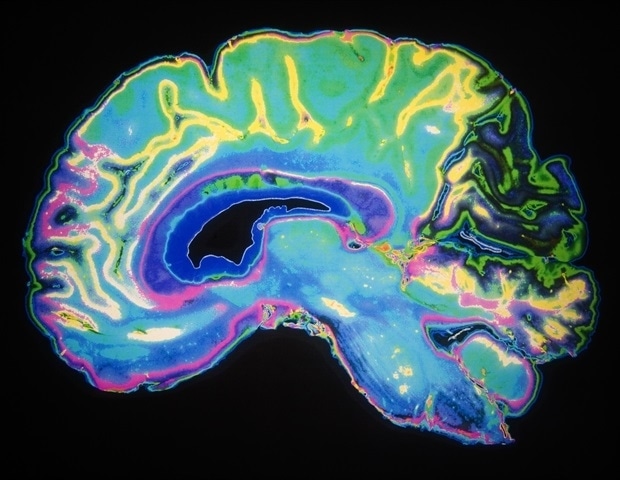

Η στοχευμένη ακτινοβολία έχει αποδειχθεί αποτελεσματική στη θεραπεία εγκεφαλικών όγκων, ωστόσο, η διάκριση της πιθανής νεκρώσεως στις θεραπευμένες περιοχές από τους όγκους σε μια τυπική μαγνητική τομογραφία (MRI) μπορεί να είναι δύσκολη. Μια νέα μελέτη που δημοσιεύθηκε σήμερα, υπό την καθοδήγηση καθηγητή του Πανεπιστημίου Γιόρκ από τη Σχολή Μηχανικών Λασόντ, αποκαλύπτει ότι μια καινοτόμος μέθοδος βασισμένη στην τεχνητή νοημοσύνη (AI) μπορεί να διακρίνει καλύτερα μεταξύ αυτών των δύο τύπων βλαβών σε προχωρημένες MRI, σε σύγκριση με την ανθρώπινη αντίληψη.

Η μελέτη αποδεικνύει, για πρώτη φορά, ότι οι νέες μέθοδοι AI που καθοδηγούνται από την προσοχή, σε συνδυασμό με προηγμένες τεχνικές MRI, μπορούν να διακρίνουν με υψηλή ακρίβεια την πρόοδο των όγκων από τη νεκρώση που προκαλείται από την ακτινοθεραπεία σε ασθενείς με μεταστάσεις στον εγκέφαλο που έχουν υποβληθεί σε στερεοτακτική ακτινοχειρουργική. Η έγκαιρη διάκριση μεταξύ αυτών των δύο καταστάσεων είναι κρίσιμη στα κέντρα καρκίνου, καθώς απαιτούν εντελώς διαφορετικές προσεγγίσεις θεραπείας.

Ο Δρ. Σαντεγκί-Ναϊνί και οι συνεργάτες του ανέπτυξαν ένα μοντέλο 3D βαθιάς μάθησης AI με δύο προηγμένους μηχανισμούς προσοχής για να διακρίνουν μεταξύ της πρόοδου των όγκων και της νεκρώσεως από την ακτινοβολία, χρησιμοποιώντας μια εξειδικευμένη τεχνική MRI, που ονομάζεται χημική ανταλλαγή κορεσμού (CEST). Η μελέτη τους έδειξε ότι η AI ήταν σε θέση να διακρίνει τις δύο καταστάσεις με ακρίβεια άνω του 85%. Στην αντίθεση, με μια τυπική MRI, οι δύο καταστάσεις διαγιγνώσκονται με ακρίβεια περίπου 60% και με πιο προηγμένες τεχνικές MRI, το ποσοστό αυτό φτάνει το 70%.